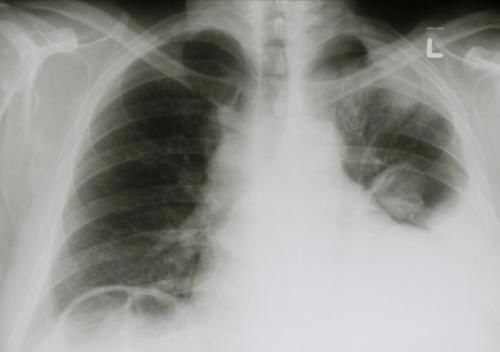

1、恶性胸腔积液

胸腔积液在肺癌中的发生率约为 7~23%,其中恶性胸腔积液约占胸腔积液的 90~95%,患者主要表现为进行性加重的呼吸困难、胸痛和干咳。呼吸困难的程度与胸腔积液量的多少、胸液形成的速度和患者本身的肺功能状态有关。

当积液量少或形成速度缓慢,患者呼吸困难较轻,仅有胸闷、气短等;若积液量大则肺脏受压明显,患者呼吸困难程度加重,甚至可能出现端坐呼吸、发绀等。